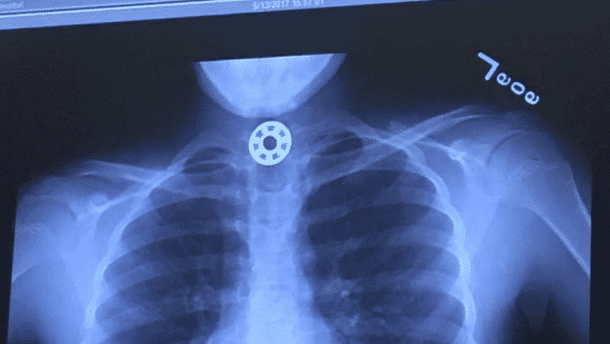

Le scanner montre clairement ce que la fillette avait ingurgité. Le docteur était tellement étonné car il venait d’apprendre ce matin même, alors qu’il se baladait avec son fils dans un centre commercial, ce qu’était un hand spinner. Quelques heures plus tard, il était amené à opérer la première victime du jouet. La petite pièce a pu être délogée et la fillette ne s’est pas étouffée. Il faut tout de même rester vigilant lors de l’utilisation de certains jouets par des jeunes enfants.

Le scanner indique clairement ou s’est logée la pièce (Facebook/Kelly Rose Joniec)